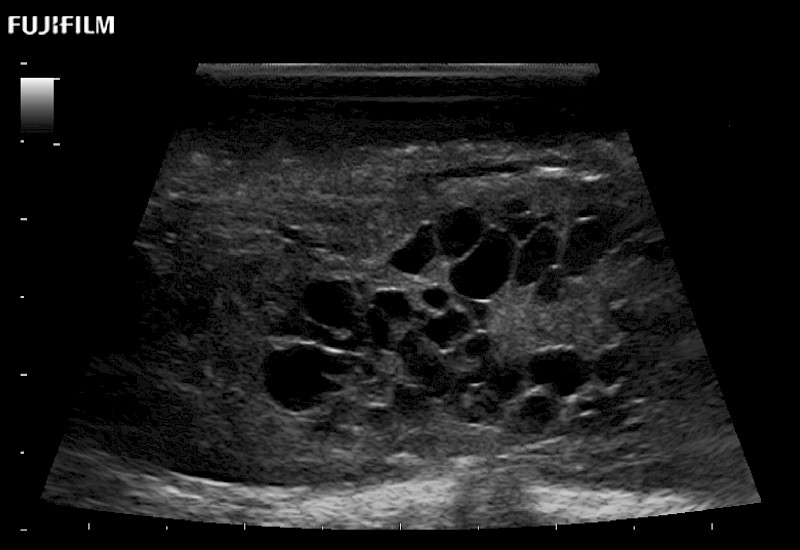

Tight curved (12mm) array transducer that is ideal for scanning during cranial guidance procedures.

Main Specifications:

Smaller footprint (20mm) curved array transducer that is ideal for scanning during cranial guidance procedures.